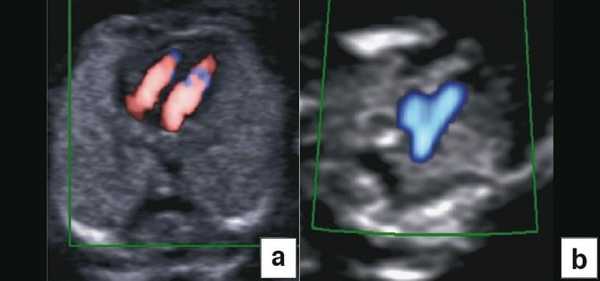

Рис. 4. Диагностика хориальности и количества амнионов в I триместре путем оценки лямбда-признака (a) и T-признака (b).